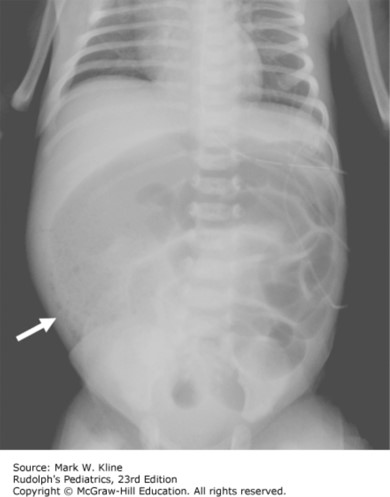

The team is notified of thick meconium-stained fluid and persistent variable heart rate decelerations with slow recovery to baseline for the past 30 minutes. The mother had spontaneous rupture of membranes approximately 20 hours ago. Vacuum-assisted vaginal delivery is being attempted as the team enters the room. The infant is delivered after two pulls on the vacuum device. There was one pop-off of the vacuum device between attempts. The infant is handed to the waiting neonatal intensive care unit (NICU) team for assessment and treatment. He is not crying, has no spontaneous respirations, appears limp and cyanotic, and has a heart rate of 75 bpm.

The correct answer is “D.” This newborn remains nonvigorous at the time of delivery with meconium present. Therefore, he should be intubated immediately (prior to any stimulation) and the trachea should be suctioned. A vigorous newborn is defined as an infant who has strong respiratory efforts, good muscle tone, and a heart rate greater than 100 bpm. If the newborn is vigorous despite the presence of meconium, suction the mouth and nose only. If the newborn in this case remains nonvigorous after intubation and suctioning of the trachea, then additional resuscitation should be undertaken promptly.

Photo: Kline MW. Rudolph's Pediatrics, 23e; 2018